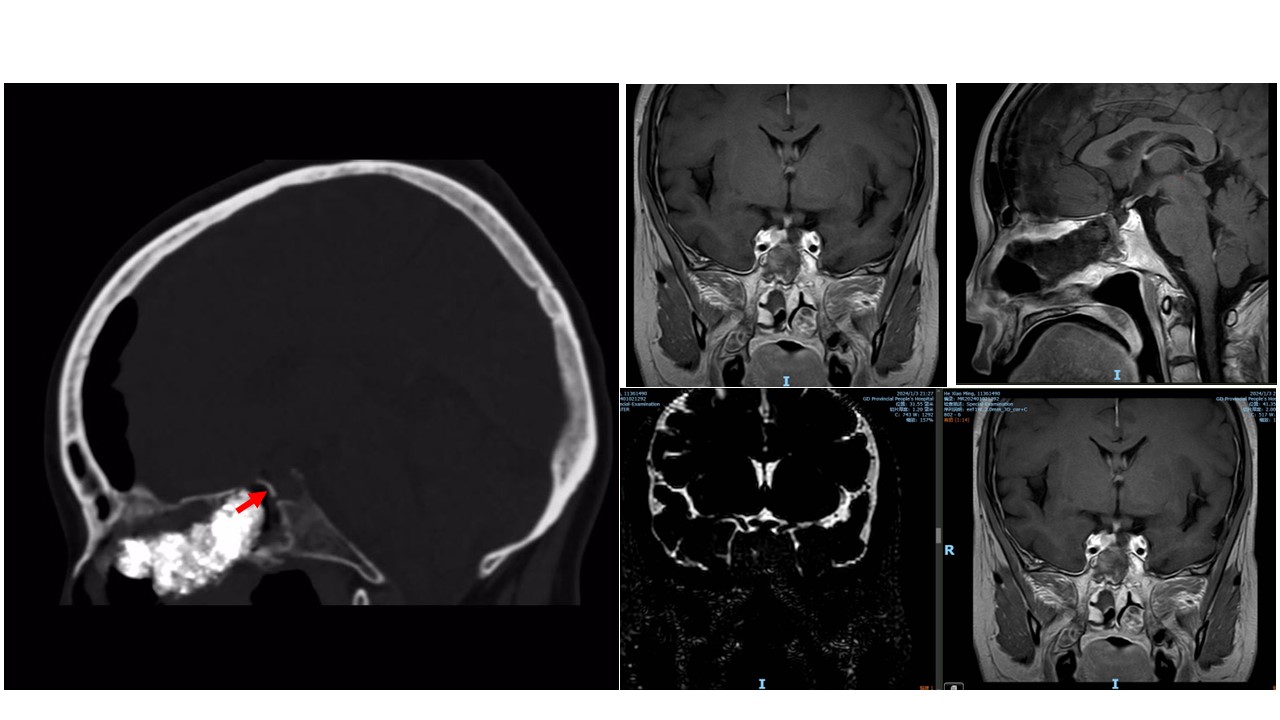

术后复查CT和磁共振